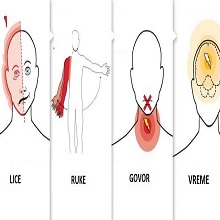

| Акутни мождани удар (инфаркт мозга, инсулт, шлог, мождана кап) је болест која настаје услед запушења крвног суда (акутни исхемијски мождани удар- 75-80% болесника) или прскања крвног суда и изливања крви у мозак или око мозга (акутни хеморагијски мождани удар - 20-25% болесника). |